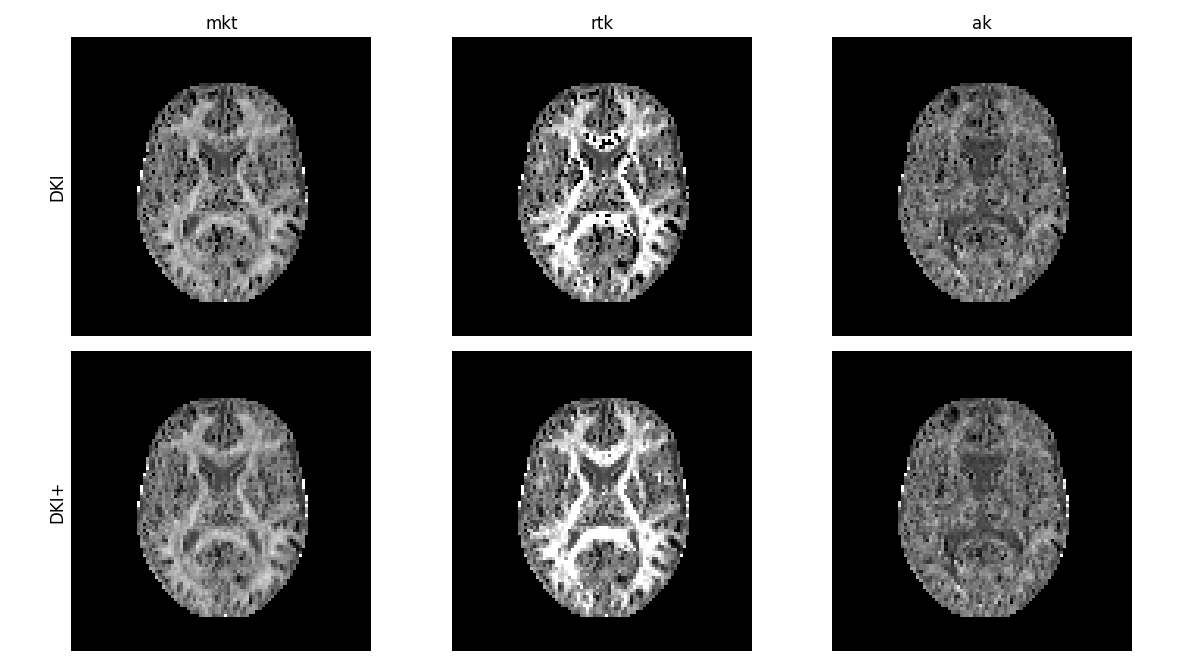

We can now compare the kurtosis measures obtained with the constrained fit to the measures obtained before, where we see that many of the artifactual voxels have now been corrected. In particular outliers caused by pure noise – instead of for example acquisition artifacts – can be corrected with this method.

compare_maps(

[dkifit, dkifit_plus],

["mkt", "rtk", "ak"],

fit_labels=["DKI", "DKI+"],

map_kwargs={"vmin": 0, "vmax": 1.5},

filename="Alternative_DKI_measures_comparison_to_DKIplus.png",

)

DKI standard kurtosis measures obtained with constrained optimization.